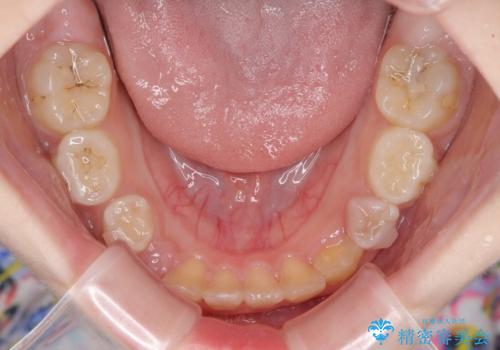

- 前歯の叢生を気にして来院された、小学校3年生女児の患者様です。

身長がやや低く、乳歯から永久歯への交換が少し遅い印象があったので、ワイヤー装置による1期矯正治療ではなく、乳歯も積極的に動かすことのできるインビザライン・ファーストにて治療を行うこととしました。

上顎前歯に過剰歯があったため、まずはその歯を抜歯し、傷が治癒したタイミングでインビザラインを発注することとしました。

インビザライン・ファーストは1.5年から2年程度の治療期間という制約がありますが、成人矯正(2期治療)をスムーズに行うための下準備期間として位置づけられており、2期治療を比較的安価かつ短期間で行うことができるようになります。